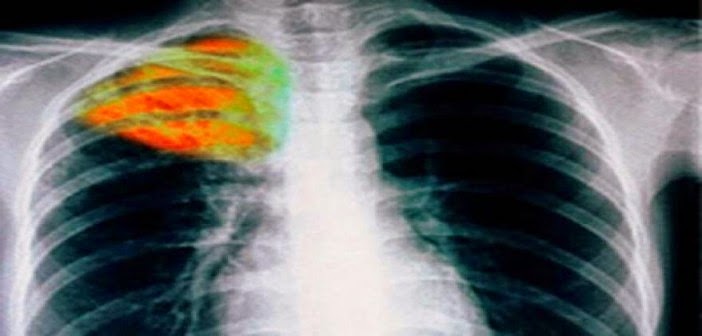

Στα πλαίσια της Παγκόσμιας Ημέρας Φυματίωσης στις 24 Μαρτίου η ΚΕΔΕ στηρίζει την συλλογική προσπάθεια για την ενημέρωση, πρόληψη, διάγνωση, αντιμετώπιση και θεραπεία της νόσου.

«Η φυματίωση είναι μία ασθένεια με ιστορία αλλά ταυτόχρονα και πολύ επίκαιρη. Η οικονομική κρίση σε συνδυασμό με τις συνεχείς γεωπολιτικές μεταβολές είναι βασικοί παράγοντες εξάπλωσης της νόσου, γεγονός που καθιστά επιτακτική την ανάγκη να συμπορευθούμε, Τοπική Αυτοδιοίκηση και Επιστημονική Κοινότητα στην κοινή προσπάθεια για την πρόληψη και αποτελεσματική θεραπεία της νόσου.